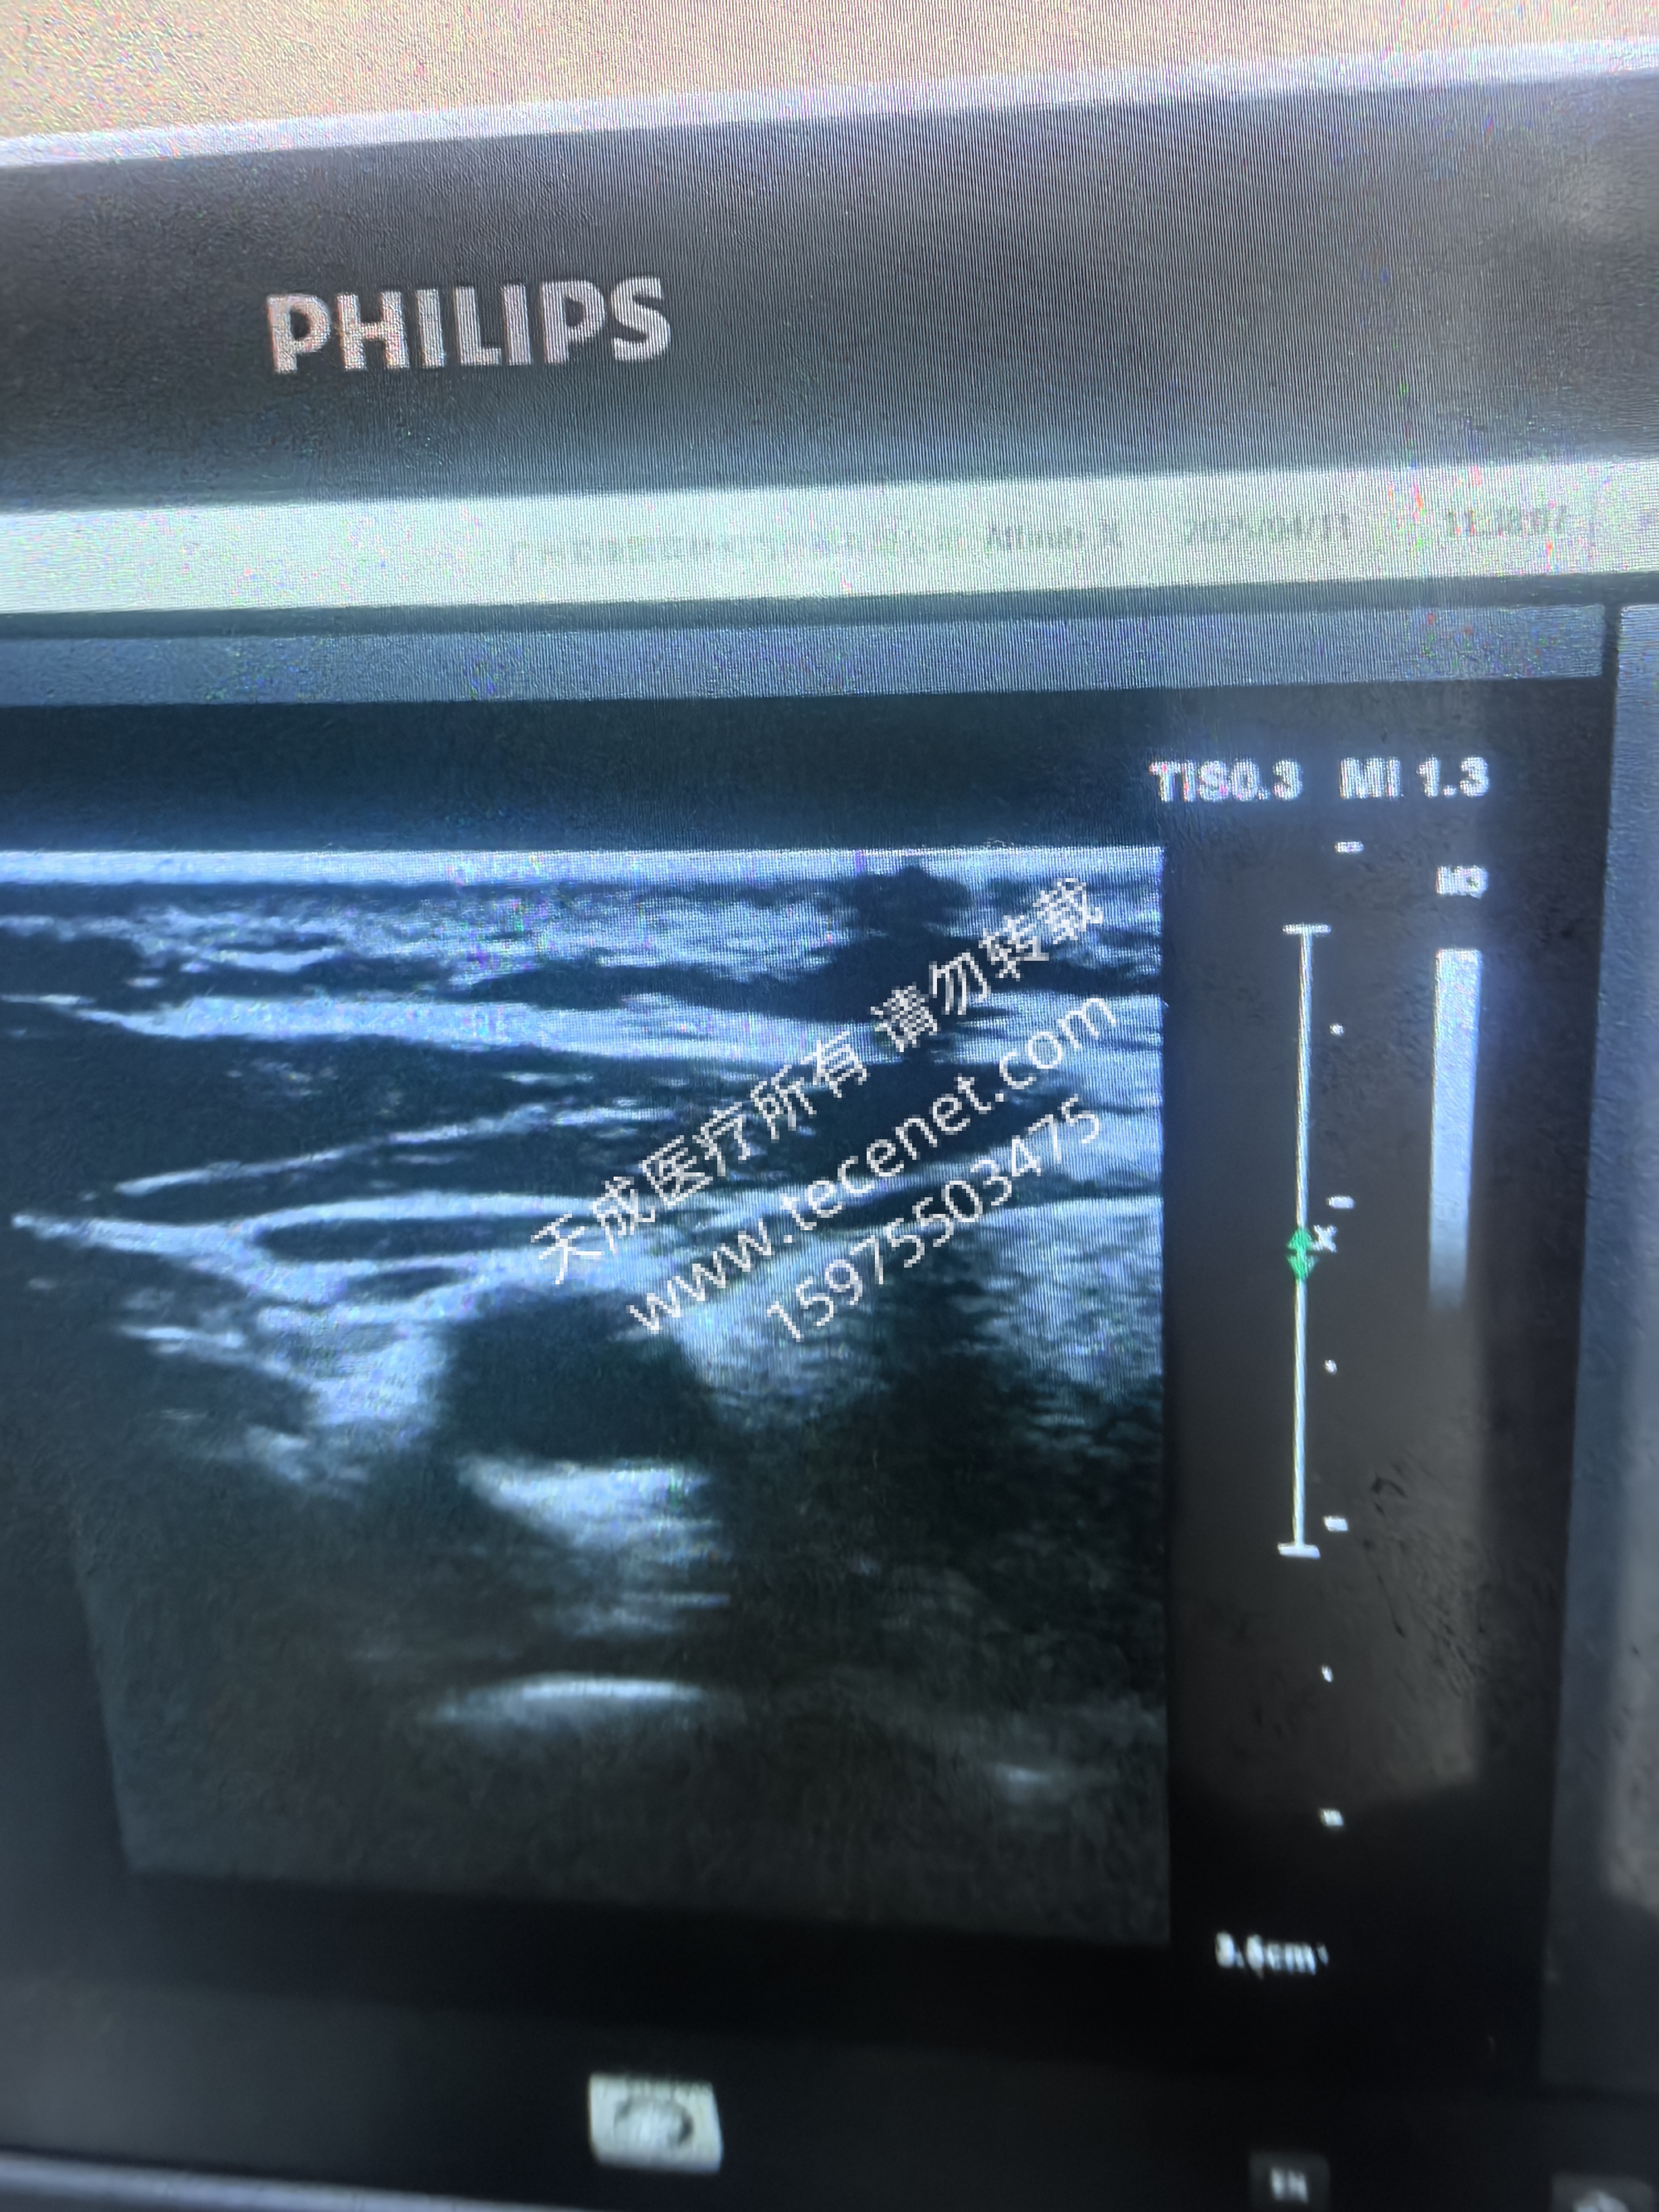

超聲探頭圖像異常

· 陣元衰減/缺失:表現(xiàn)為圖像局部暗塊或缺失,需通過專業(yè)設(shè)備檢測晶片狀態(tài)(如L12-3探頭30個陣元失效案例)

· 聲透鏡破損:圖像出現(xiàn)黑影或鼓包,需更換透鏡并注意避免使用油性耦合劑腐蝕透鏡

· 電磁干擾:通過電網(wǎng)或未屏蔽線纜引入,表現(xiàn)為波紋狀/滾動條干擾,需優(yōu)化接地或更換電源插座